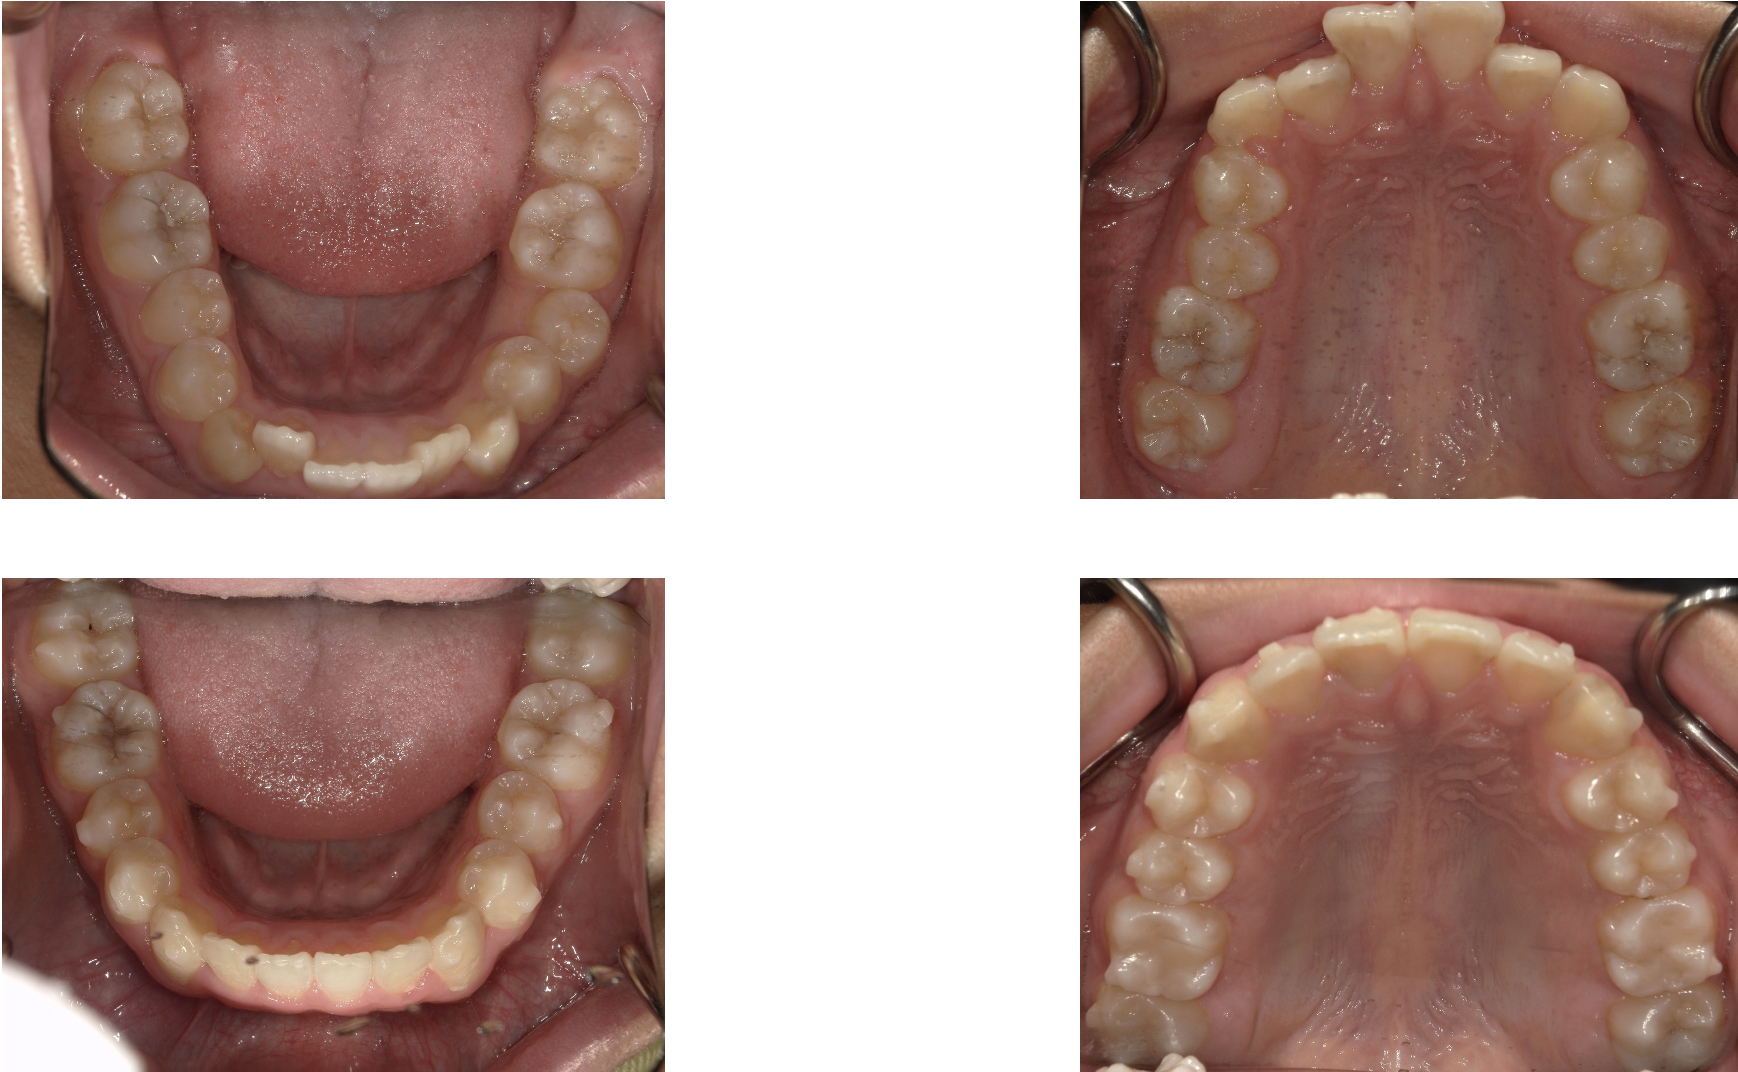

インビザライン矯正で全体的な歯並びを改善した症例

インビザライン矯正を行って歯列矯正を行った症例